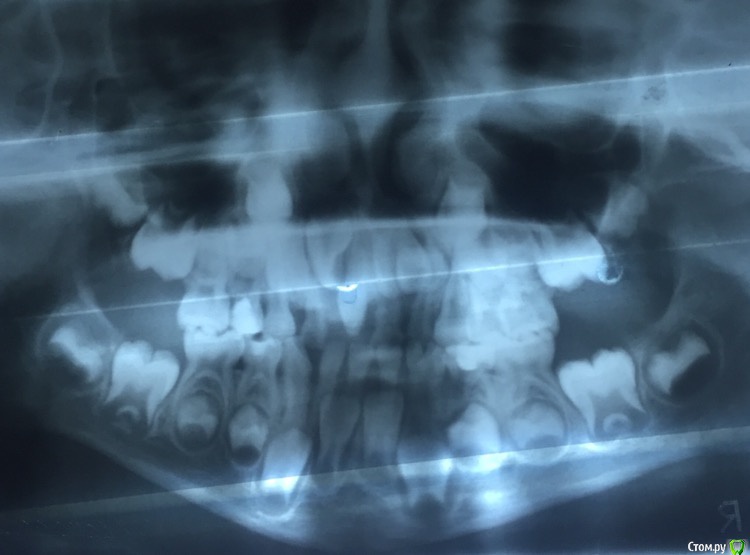

Vitalina_angel Опубликовано 20 апреля, 2016 Автор Поделиться Опубликовано 20 апреля, 2016 Вот вроде получилось, надеюсь посмотрите и мне расскажите что и как. Ссылка на комментарий

___49___ Опубликовано 20 апреля, 2016 Поделиться Опубликовано 20 апреля, 2016 (изменено) По снимку определяется сдвиг зачатка 22 зуба в сторону клыка за счет контакта с вестибулярной поверхностью зачатка 21 зуба повернутого по оси на 90 градусов из-за сверхкомплектного зуба. Путь удаления S вижу с вектором направленным к центральной линии под острым углом, захват с предварительным рассечением по гребню от 51 до 62 с последующей отслойкой ,и малыми ротационными движениями должен прекрасно извлечься без всякого "ковыряния". .. и с более благоприятным отдаленным результатом. ИМХО. Расписал удаление подробно для коллег - если ошибаюсь - поправьте . Изменено 20 апреля, 2016 пользователем ___49___ Ссылка на комментарий